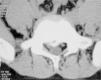

Finalmente, se debe considerar que la biología músculo-esquelética varía de manera importante según la edad, determinando que distintas condiciones predominen en distintos grupos etarios. La patología degenerativa por supuesto predomina en el atleta adulto y las diferencias inherentes del esqueleto en el atleta juvenil resultan en la presencia de lesiones casi exclusivamente de este grupo. La fractura marginal de la placa vertebral o fractura limbus es un ejemplo de ello (Figura 1). El adolescente mayor y el adulto joven representan una situación intermedia en este aspecto y a veces no resulta fácil predecir los hallazgos que ofrecerán las imágenes, pudiendo surgir lesiones del tipo degenerativo como lesiones propias de una fisis juvenil.

Fractura limbus del nivel L4L5 en un joven futbolista de 14 años. Nótese la importante reducción en el canal central. La presentación clínica era de rigidez lumbar dolorosa con marcada retracción de isquiotibilales. Por persistencia de síntomas con imposibilidad de retornar al entrenamiento luego de un período prolongado de tratamiento conservador, se sometió a una decompresión posterior mediante laminotomía bilateral, respetando las articulaciones facetarias. Excelente evolución con retorno deportivo a las 6 semanas. La retracción de isquiotibiales, como suele ser en estos casos, persistió por más de 6 meses luego de la cirugía.

Fractura limbus vertebralEsta lesión anatómica corresponde a una fractura-deslizamiento de la placa superior de la vértebra, que resulta en la ocupación parcial del canal raquídeo por un fragmento osteo-cartilaginoso, con un efecto compresivo que se expresa como lumbociática. El clínico debe tener en consideración que el fragmento casi invariablemente es central y la manifestación clínica comúnmente es dolor predominantemente lumbar con irradiación ciática incompleta y bilateral y acortamiento marcado de isquiotibiales. La lesión se puede diagnosticar muy claramente con una TAC que la detalla más claramente que la RM. Excepcionalmente la magnitud de la compresión lleva a un déficit neurológico. En la gran mayoría de los casos la ausencia del déficit permite un manejo conservador inicial, que incluye reposo deportivo, analgesia y fisioterapia. Frente a la persistencia de síntomas, se debe proceder a una cirugía descompresiva posterior. El autor ha visto demasiados casos en que se comete el error de replicar la cirugía de HNP que se realiza habitualmente en un adulto, la laminotomía unilateral y resección del fragmento extruido, resultando en una descompresión incompleta que resulta no solo en alivio incompleto, sino que provoca edema postoperatorio en un canal estenótico con resultado de una cauda equina postoperatoria. La cirugía de estos casos entonces requiere de una descompresión amplia, idealmente mediante laminotomia bilateral, que de cuenta de la estenosis del canal. La resección del fragmento no es siempre necesaria y depende de su tamaño y localización.